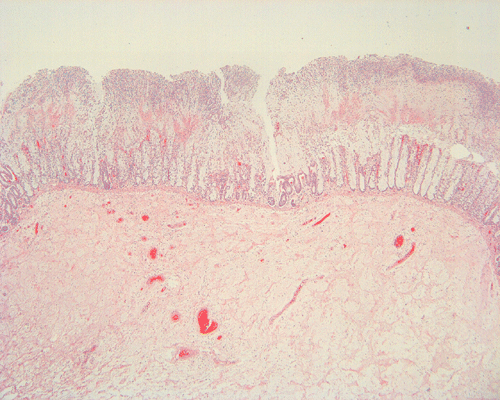

Histopathology: On scanning magnification, the mucosa has a sandwich like structure (Panel A). At the bottom is a layer of partially destroyed glands with a middle layer of mucoid material and topped by a layer of inflammatory exudate (Ž in Panel A). In some areas, the inflammatory exudate takes the shape of a mushroom or volcano (Panel B). The submucosa is edematous but lacks significant inflammatory cell infiltration. The top layer of inflammatory exudate is composed exclusively of degenerated polymorphonuclear leukocytes (Panel C and D). At the base of the mucosa, the outline of the normal glandular architecture is maintained but there is intense infiltration by polymorphonuclear leukocytes in the lamina propria (Panel E and F). On high-magnification, the crypts are filled by signet ring cells. In severely inflammed areas, there are some single singnet ring cells in the lamina propria (Panel G). In the deeper part of the mucosa where inflammation is not as intense, the boundary between the crypts and the lamina is respected by the signet cells (Panel H). In the more superficial part of the mucosa, the glandular architecture is disrupted (Panel I). Sporadic signet ring cells are also found in mucosa that are relatively unaffected (Panel J).

Macroscopically, membranous colitis is featured by erythematous, denuded mucosa with scattered patches of grayish-white to yellow plaques or pseudo-membranes and a thickened lamina propria. Microscopically, the mucosa shows a dense infiltrate of neutrophils within the superficial lamina propria, denudement of surface epithelium, and occasional capillary fibrin thrombi. Mucopurulent exudate fills distended crypts and erupts into the bowel lumen to form a pseudo-membrane adherent to the damaged epithelial surface 5. In the most typical case, the pseudomembrane and the damaged mucosa give resemblance to an erupting vocano.